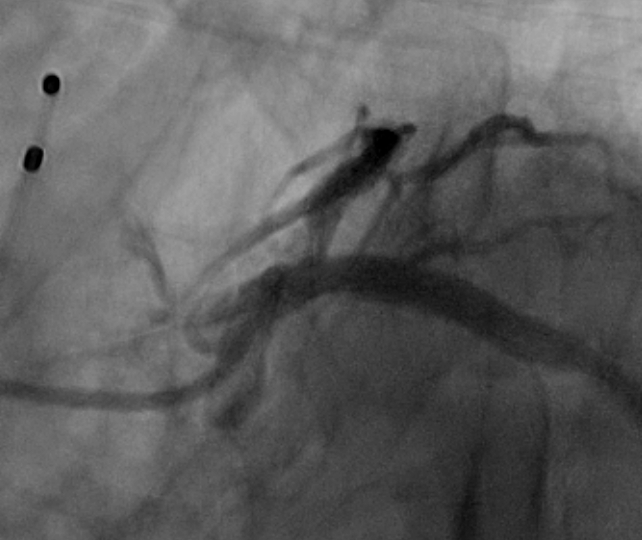

冠状动脉性心脏病,前列腺增生术后;

左主干及前降支重度钙化伴严重狭窄。

唐熠达教授团队对病例进行多学科综合分析评估决定行一站式PCI+TAVI手术,结合患者91岁高龄,主动脉根部结构及双侧劲动脉粥样硬化斑块形成,脑动脉硬化情况采用20mm球囊预扩,拟植入VenusA-Valve L26瓣膜。

根部造影

术后造影

瓣膜定位精准,标准位释放,轻微瓣周漏,术后效果良好,手术取得圆满成功。